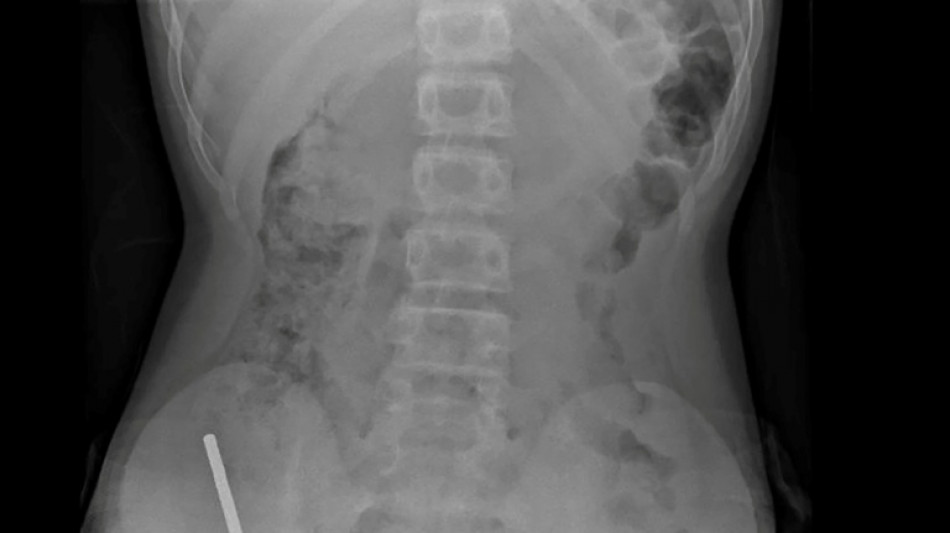

Nouvelle-Zélande: un adolescent opéré après avoir ingéré près de 100 aimants achetés sur Temu / Photo: © NEW ZEALAND MEDICAL JOURNAL (NZMDJ)/AFP

"Il avoué avoir ingéré entre 80 et 100 aimants puissants au néodyme, de 5x2mm environ, une semaine plus tôt", indique un rapport des médecins de l'hôpital de cet hôpital, publié dans le New Zealand Medical Journal (NZMJ).

Les médecins ont déclaré que la pression exercée par les aimants avait provoqué une nécrose dans quatre zones de l'intestin grêle et du gros intestin du garçon.